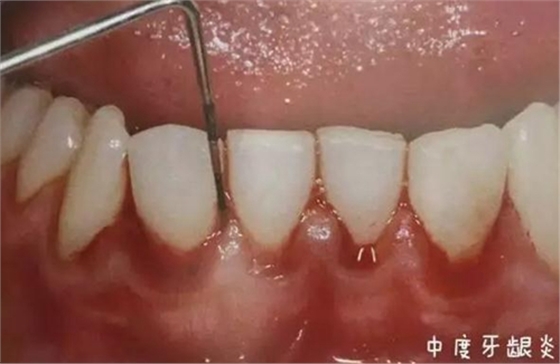

牙齦炎

區(qū)域:炎癥局限在牙齦軟組織中,主要由牙菌斑引起的。

癥狀:會(huì)造成牙齦紅腫、出血,點(diǎn)彩消失,但不會(huì)造成牙周袋也不會(huì)導(dǎo)致牙齒松動(dòng)。

在這個(gè)階段,牙齦炎還是可逆的,但是如果此時(shí)不進(jìn)行早期治療,不然牙齦炎就會(huì)進(jìn)一步發(fā)展成牙周炎,而且概率異常的高。